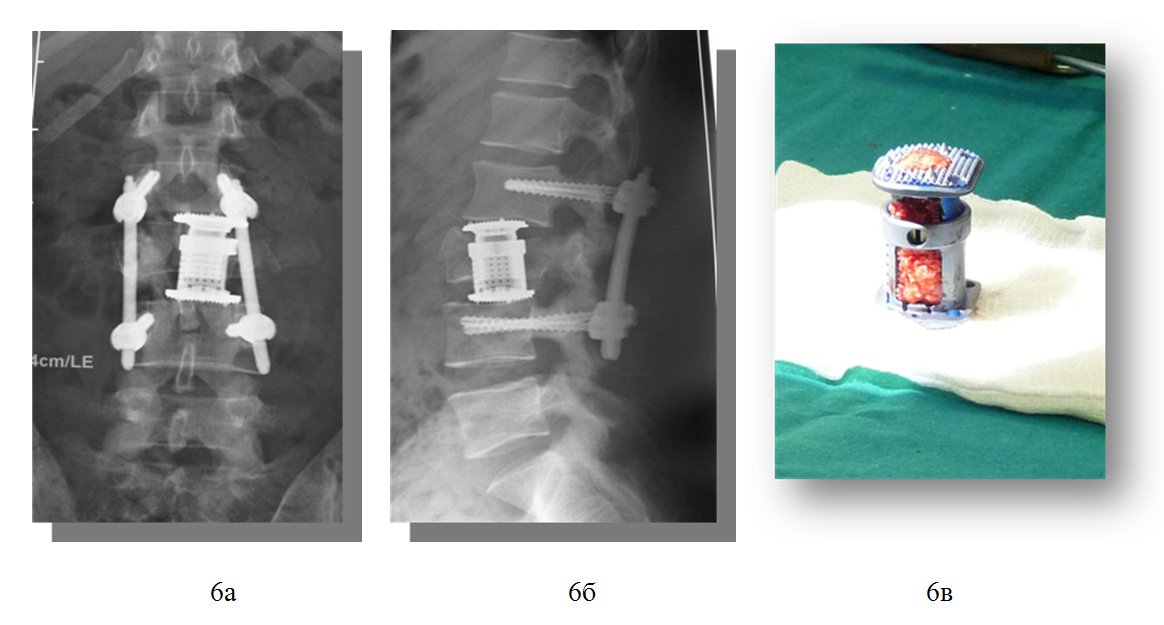

1) закрытый нестабильный, компрессионно-оскольчатый перелом тела и левого поперечного отростка 3 поясничного позвонка, перелом дуг 3-4 поясничных позвонков и субкомпенсированный стеноз позвоночного канала на уровне 3 поясничного позвонка, радикулопатия 4 поясничного корешка слева, посттравматическая кифотическая деформация позвоночника.

- Задняя внутренняя коррекция и фиксация позвоночника чрескожной транспедикулярной системой «Viper 2» De Puy-Synthes.